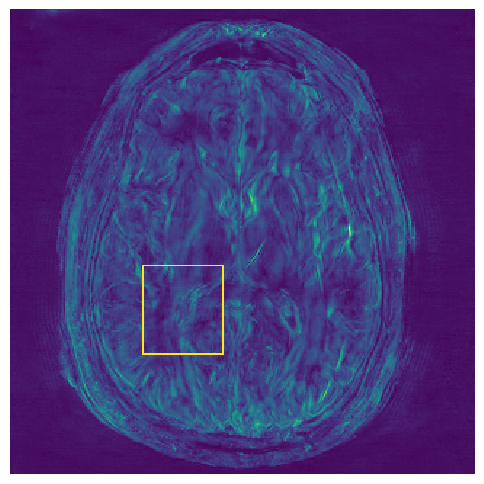

(e) Std.

Figure 3: Examples of Reconstruction Results. Rows 1 and 3: The Ground truth (GT) fully sampled image, the reconstructed images obtained by the three models (1-3), NPB-REC, baseline, E2E-VarNet trained with Dropout, and the Std. map derived from our method for acceleration rates R=4𝑅4R=4, R=8𝑅8R=8, respectively. Rows 2 and 4: The corresponding annotated ROIS of the edema and resection cavity.

Fig. 3 presents examples of reconstruction results obtained by (1) our NPB-REC approach, (2) the baseline, and (3) Monte Carlo Dropout, for equispaced masks with two different acceleration rates R=4𝑅4R=4 and R=8𝑅8R=8. Table 1 presents the mean PSNR and SSIM metrics, calculated over the whole inference set, for the three models. our NPB-REC approach achieved significant improvements over the other methods in terms of PSNR and SSIM (Wilcoxon signed-rank test, pmuch-less-than\ll1e-4). The improvement in the reconstruction performance can be noted both quantitatively from the metrics especially for masks with acceleration rate R=8𝑅8R=8 and qualitatively via the images of annotations, where our results shows less smoothness than that obtained by Dropout.